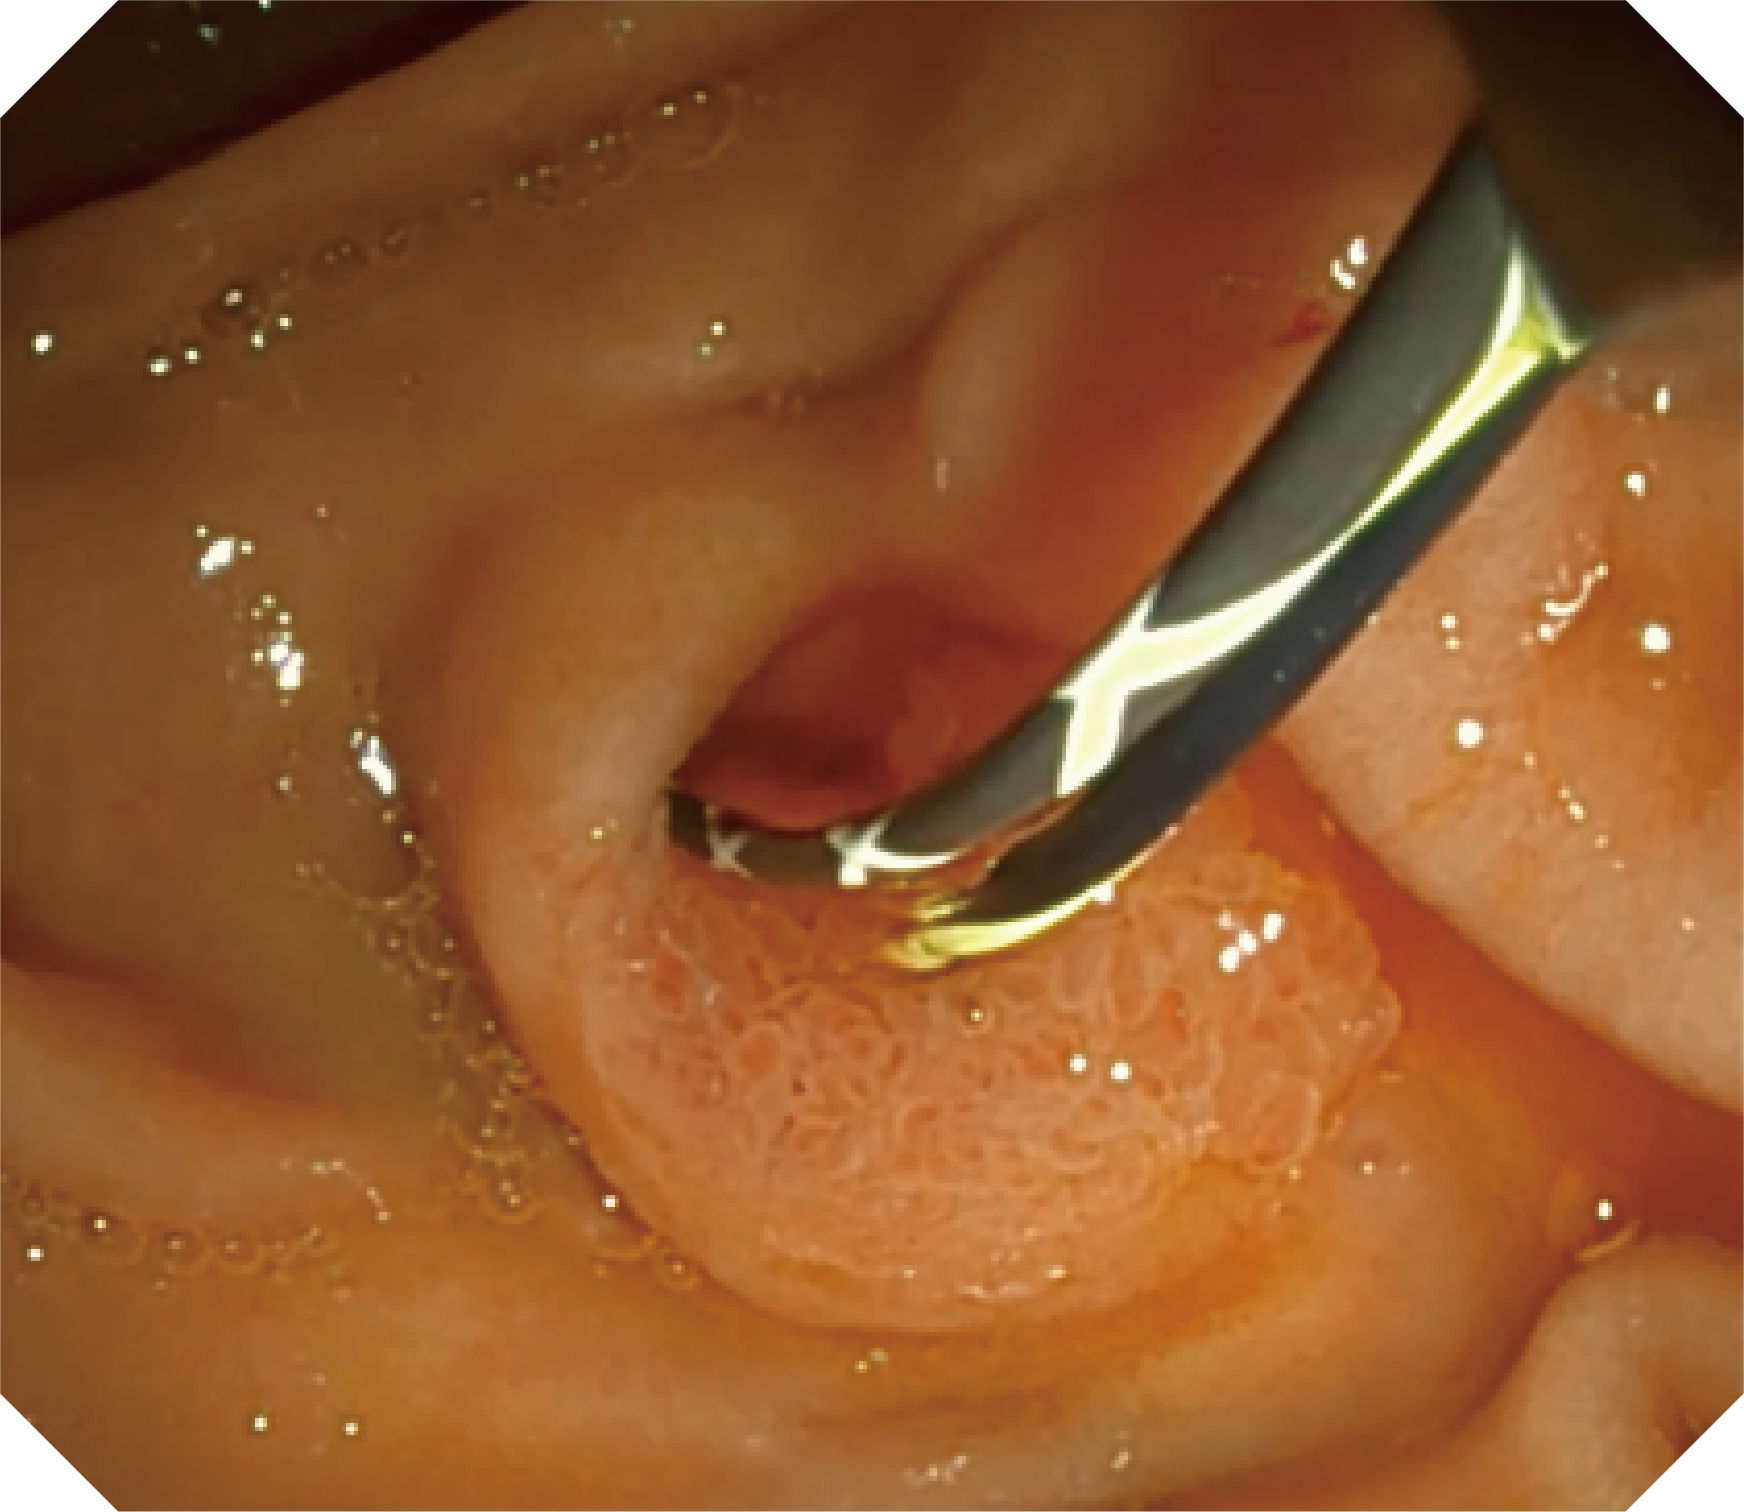

4.2mm大钳道,器械交换更顺畅

优异的手术器械抬举性

更好的通过性,更稳定的镜体支撑力